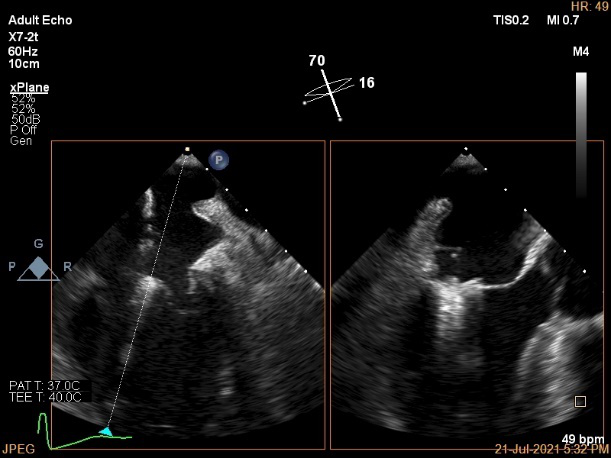

术中超声引导:

确定房间隔穿刺点:靠后

穿刺点高度测量:4.14cm

2D视图下测量大鞘长度2.2cm

2D视图下建立trajectory

3D视图打开夹子

3D视图下调Rotate,定位2区

X-plane:下夹子尝试捕获2区

夹子逐渐夹闭后,2区返流逐渐减少

3D:测量前叶长21.2mm,后叶长10.2mm

X-plane:计算前叶捕获长度6.8mm,后叶捕获长度6.5mm

夹子放置后二尖瓣口平均跨瓣压差:3mmHg

肺静脉血流频谱恢复正常

3D视图下观察二尖瓣双孔形态

3D-color:残余少量返流